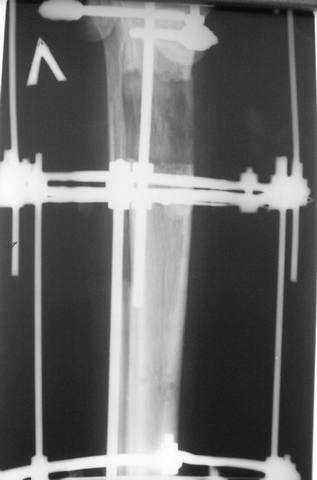

Произведено ПХО, acute shortening (5 см), фиксация стержневым аппаратом Hoffman.

3,4 - через 4 недели наложен спице-стержневой аппарат, произведена остеотомия большеберцовой кости в верхней трети, раны зажили, проводилась дистракция в аппарате.